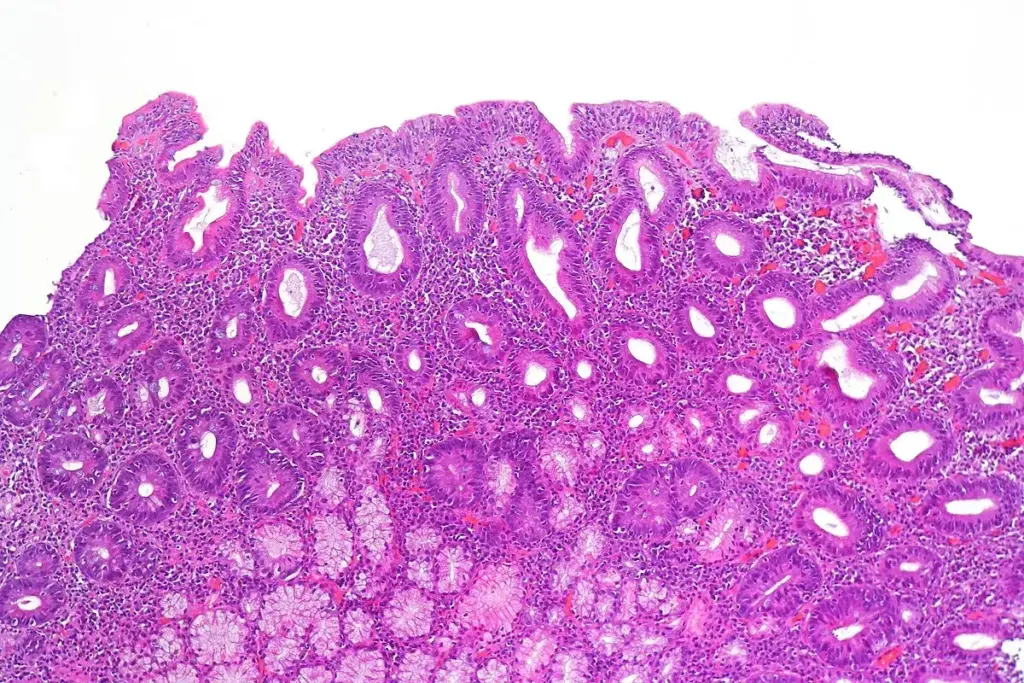

Celiac disease is an autoimmune disorder caused by gluten in people who are genetically predisposed. When people with celiac disease eat gluten, it triggers an immune reaction. This reaction damages the small intestine’s lining.

This damage can cause the body to not absorb nutrients well. This can lead to health problems.

Chronic inflammation from celiac disease can harm the body in many ways. It can cause the immune system to keep reacting and inflaming. This can lead to a higher risk of certain cancers.

Research published in AJMC shows that celiac disease is linked to different cancer risks. The inflammation from celiac disease can damage the gut and possibly other parts of the body. This damage can raise the risk of specific cancers.

Studies show that those with celiac disease who heal their intestines face less cancer risk. Intestinal healing means the small intestine’s lining is fixed. This is key because it helps the intestine work right, lowering cancer risk.

Healing the intestines is linked to sticking to a gluten-free diet. Avoiding gluten helps fix the intestine’s lining. This isn’t just about feeling better; it’s also about avoiding serious problems like cancer.